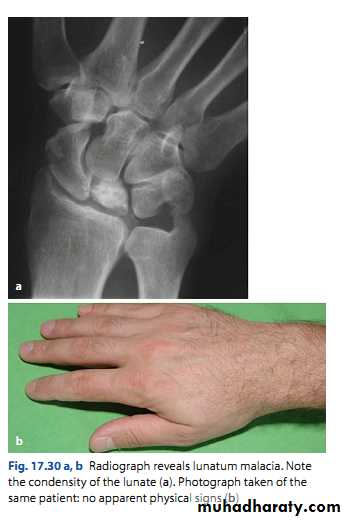

Kienbӧck’s disease

Ischemic necrosis of the lunate bone.

Associated with excessive loading of the lunate.

Clinical features:

Pain and stiffness of the wrist.

Tenderness over the lunate bone.

Limitation of movement.

4 stages:

• Ischemia without changes, normal x-ray, MRI changes.

• Trabecular necrosis, new bone formation, x-ray show increased density.

• Bone collapse; x-ray show small irregular lunate bone.

• Secondary OA of the wrist.

Early: splintage for 6-12 weaks.

Late: surgical treatment eg, wrist arthrodesis.